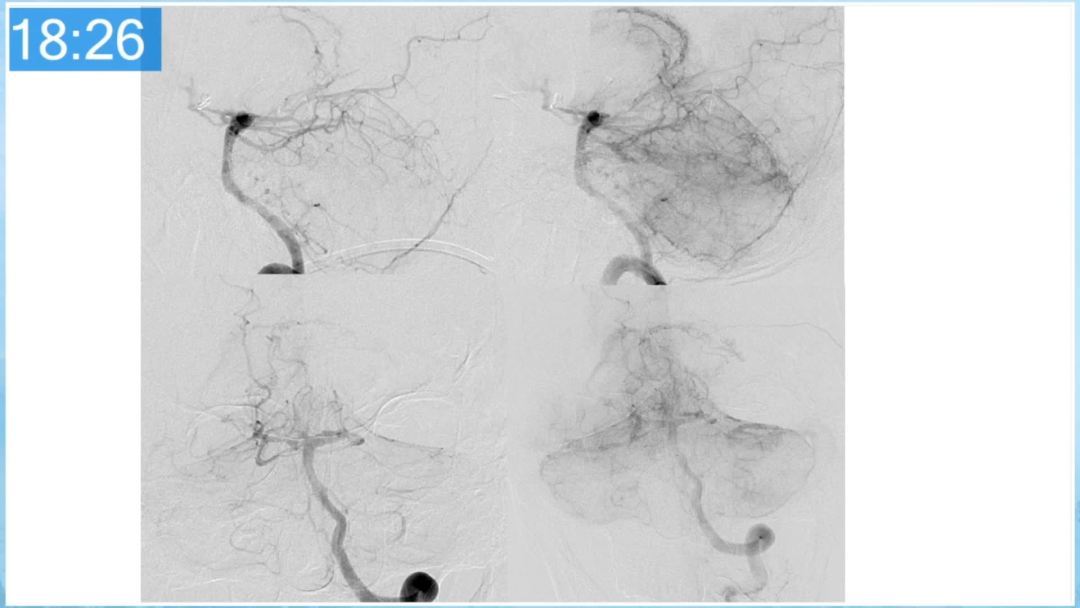

本期为大家特别分享:空军军医大学唐都医院邓剑平教授的精彩会议内容《颅内动静脉畸形的复合手术治疗》,欢迎大家阅读和分享!